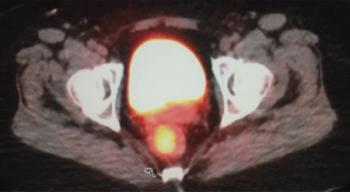

A 39-year-old Hispanic male presented with complaints of mucous stools, loss of appetite, rectal bleeding and a 30-pound weight loss within the past several months.